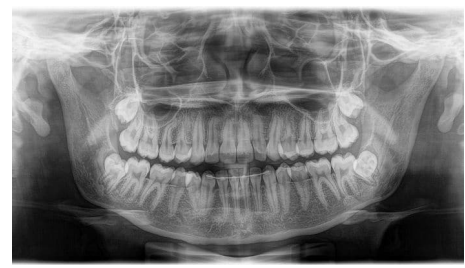

Analise a radiografia abaixo:

A imagem ilustrada refere-se de um raio-x do tipo: